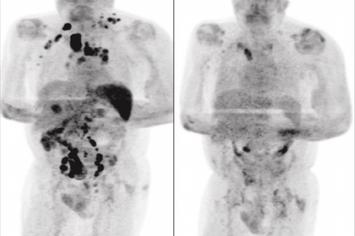

Quatro meses depois, os médicos afirmaram que o inchaço dos nódulos havia diminuído. Um exame de tomografia revelou a remissão generalizada do linfoma.

A hipótese levantada pelos autores do artigo é de que a infecção pelo novo coronavírus desencadeou uma resposta imune contra o tumor. As citocinas inflamatórias produzidas em resposta à infecção poderiam ter ativado células T específicas com antígenos tumorais e células que naturalmente agem contra o tumor.